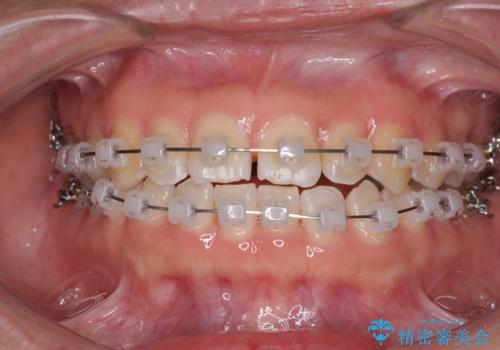

- クリアブラケット

- 治療期間

- 9ヶ月

下の前歯が上の前歯を突き上げるように咬合するため、咬み合わせの位置を改善しながら隙間を閉じていきました。